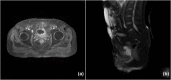

Figure 2

MRI of the pelvis confirming the presence of pubovesical fistula. Axial (a) and sagittal (b) images.